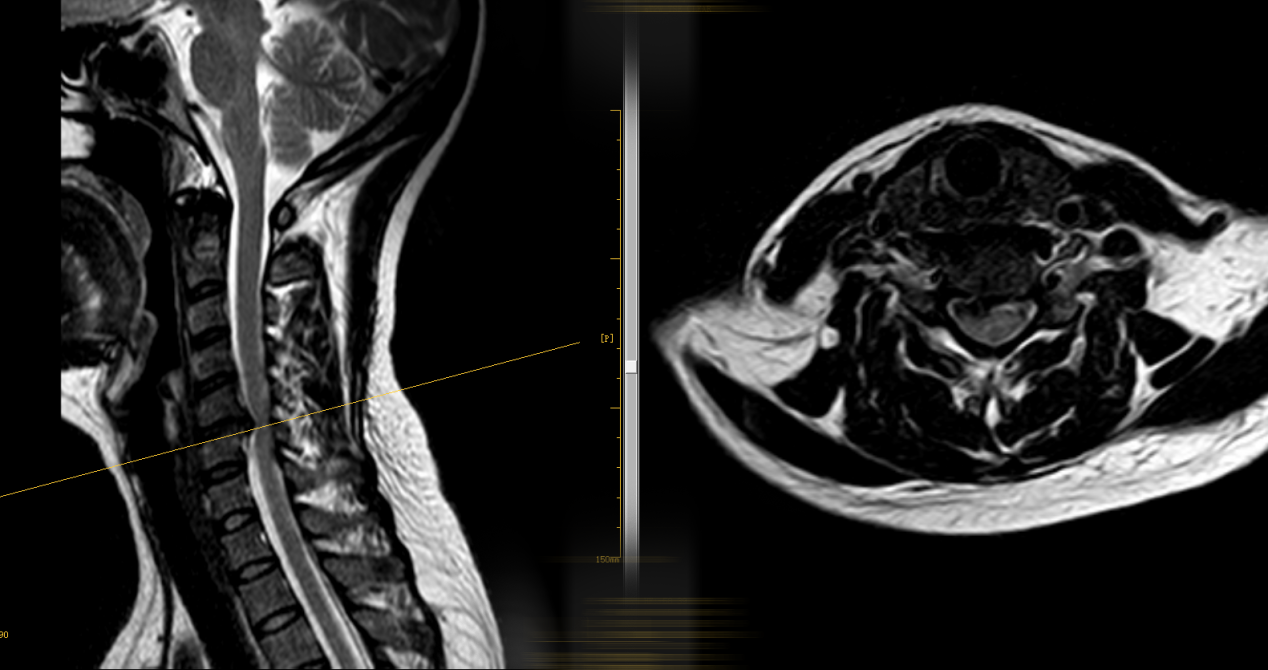

MRI检查